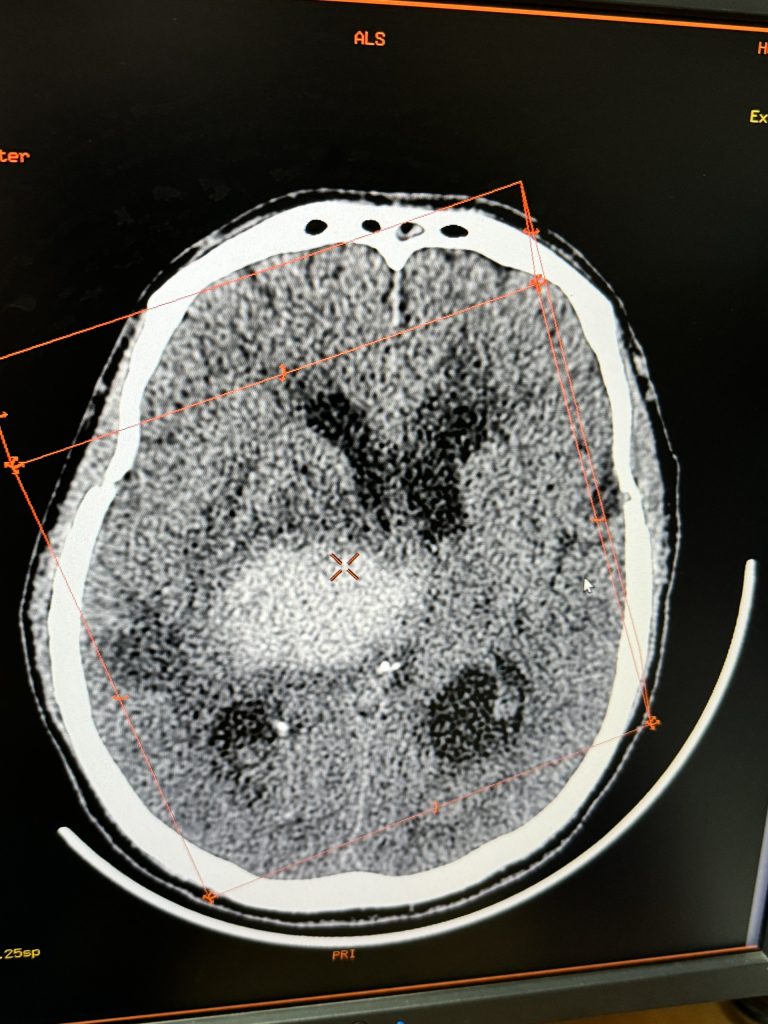

Người bệnh sau khi thăm khám và thực hiện các kỹ thuật cấp cứu: đặt nội khí quản, ống thông dạ dày, ống thông bàng quang, được chỉ định làm các cận lâm sàng cần thiết. Kết quả chụp CT cho thấy hình ảnh có ổ chảy máu nhu mô não nhân xám thần kinh trung ương phải: kích thước 37x27x35mm gây phù não xung quanh và đẩy lệch đường giữa sang trái gần khoảng 11mm gây tràn máu vào hệ thống não thất.

Sau 9 ngày điều trị, ông T được chụp lại CT sọ não kết quả cho thấy ổ chảy máu ở nhu mô kích thước nhỏ lại có dấu hiệu hóa dịch. Sau đó người bệnh được các bác sỹ hội chẩn, thống nhất tiến hành mở canuyn khí quản để thông khí xuống phổi tốt hơn, giảm nguy cơ tắc đờm ở đường thở và khi cai máy thở sẽ giảm công hô hấp cho người bệnh dễ thở hơn.